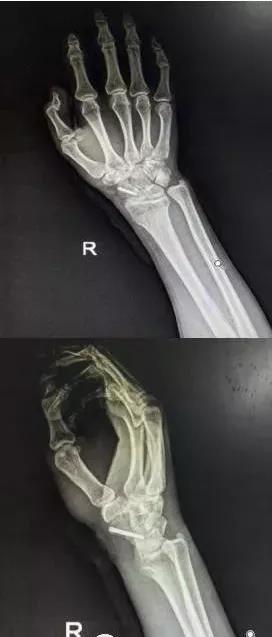

6)桡骨远端骨折

- 绝大部分骨折可以手法复位制动。

- 关节面粉碎,塌陷者应手术。

- 如果伤后拇长伸肌腱卡压,正中神经损伤者,应立即手术。